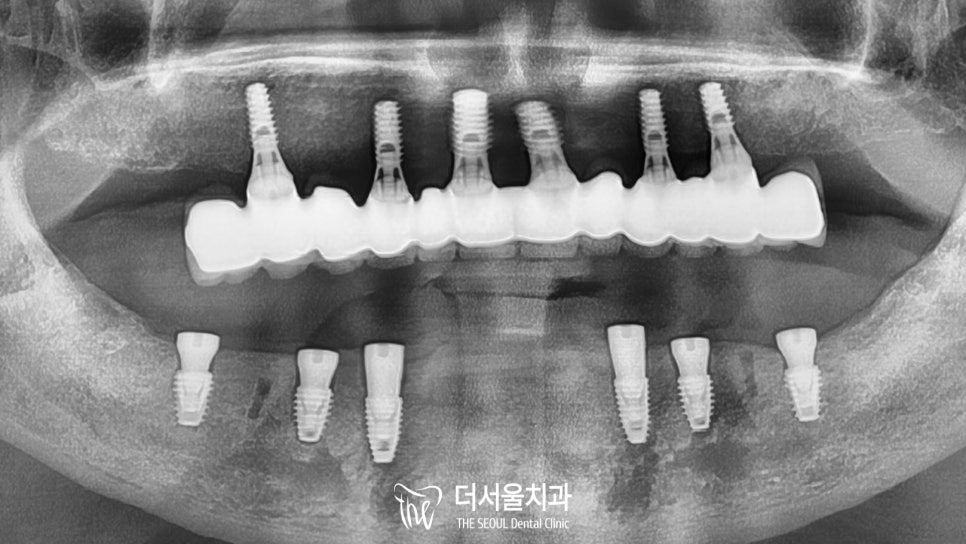

위쪽엔 임플란트 를,

아래쪽엔 틀니를 사용하고 있던 분이었습니다.

컴퓨터 분석을 토대로 결정된 식립 위치에

순차적으로 임플란트 를 심어드렸습니다.

이제 최종 보철 제작만을 앞두고 있는데요.

치료 기간 2022.08.03 ~ 2022.11.15